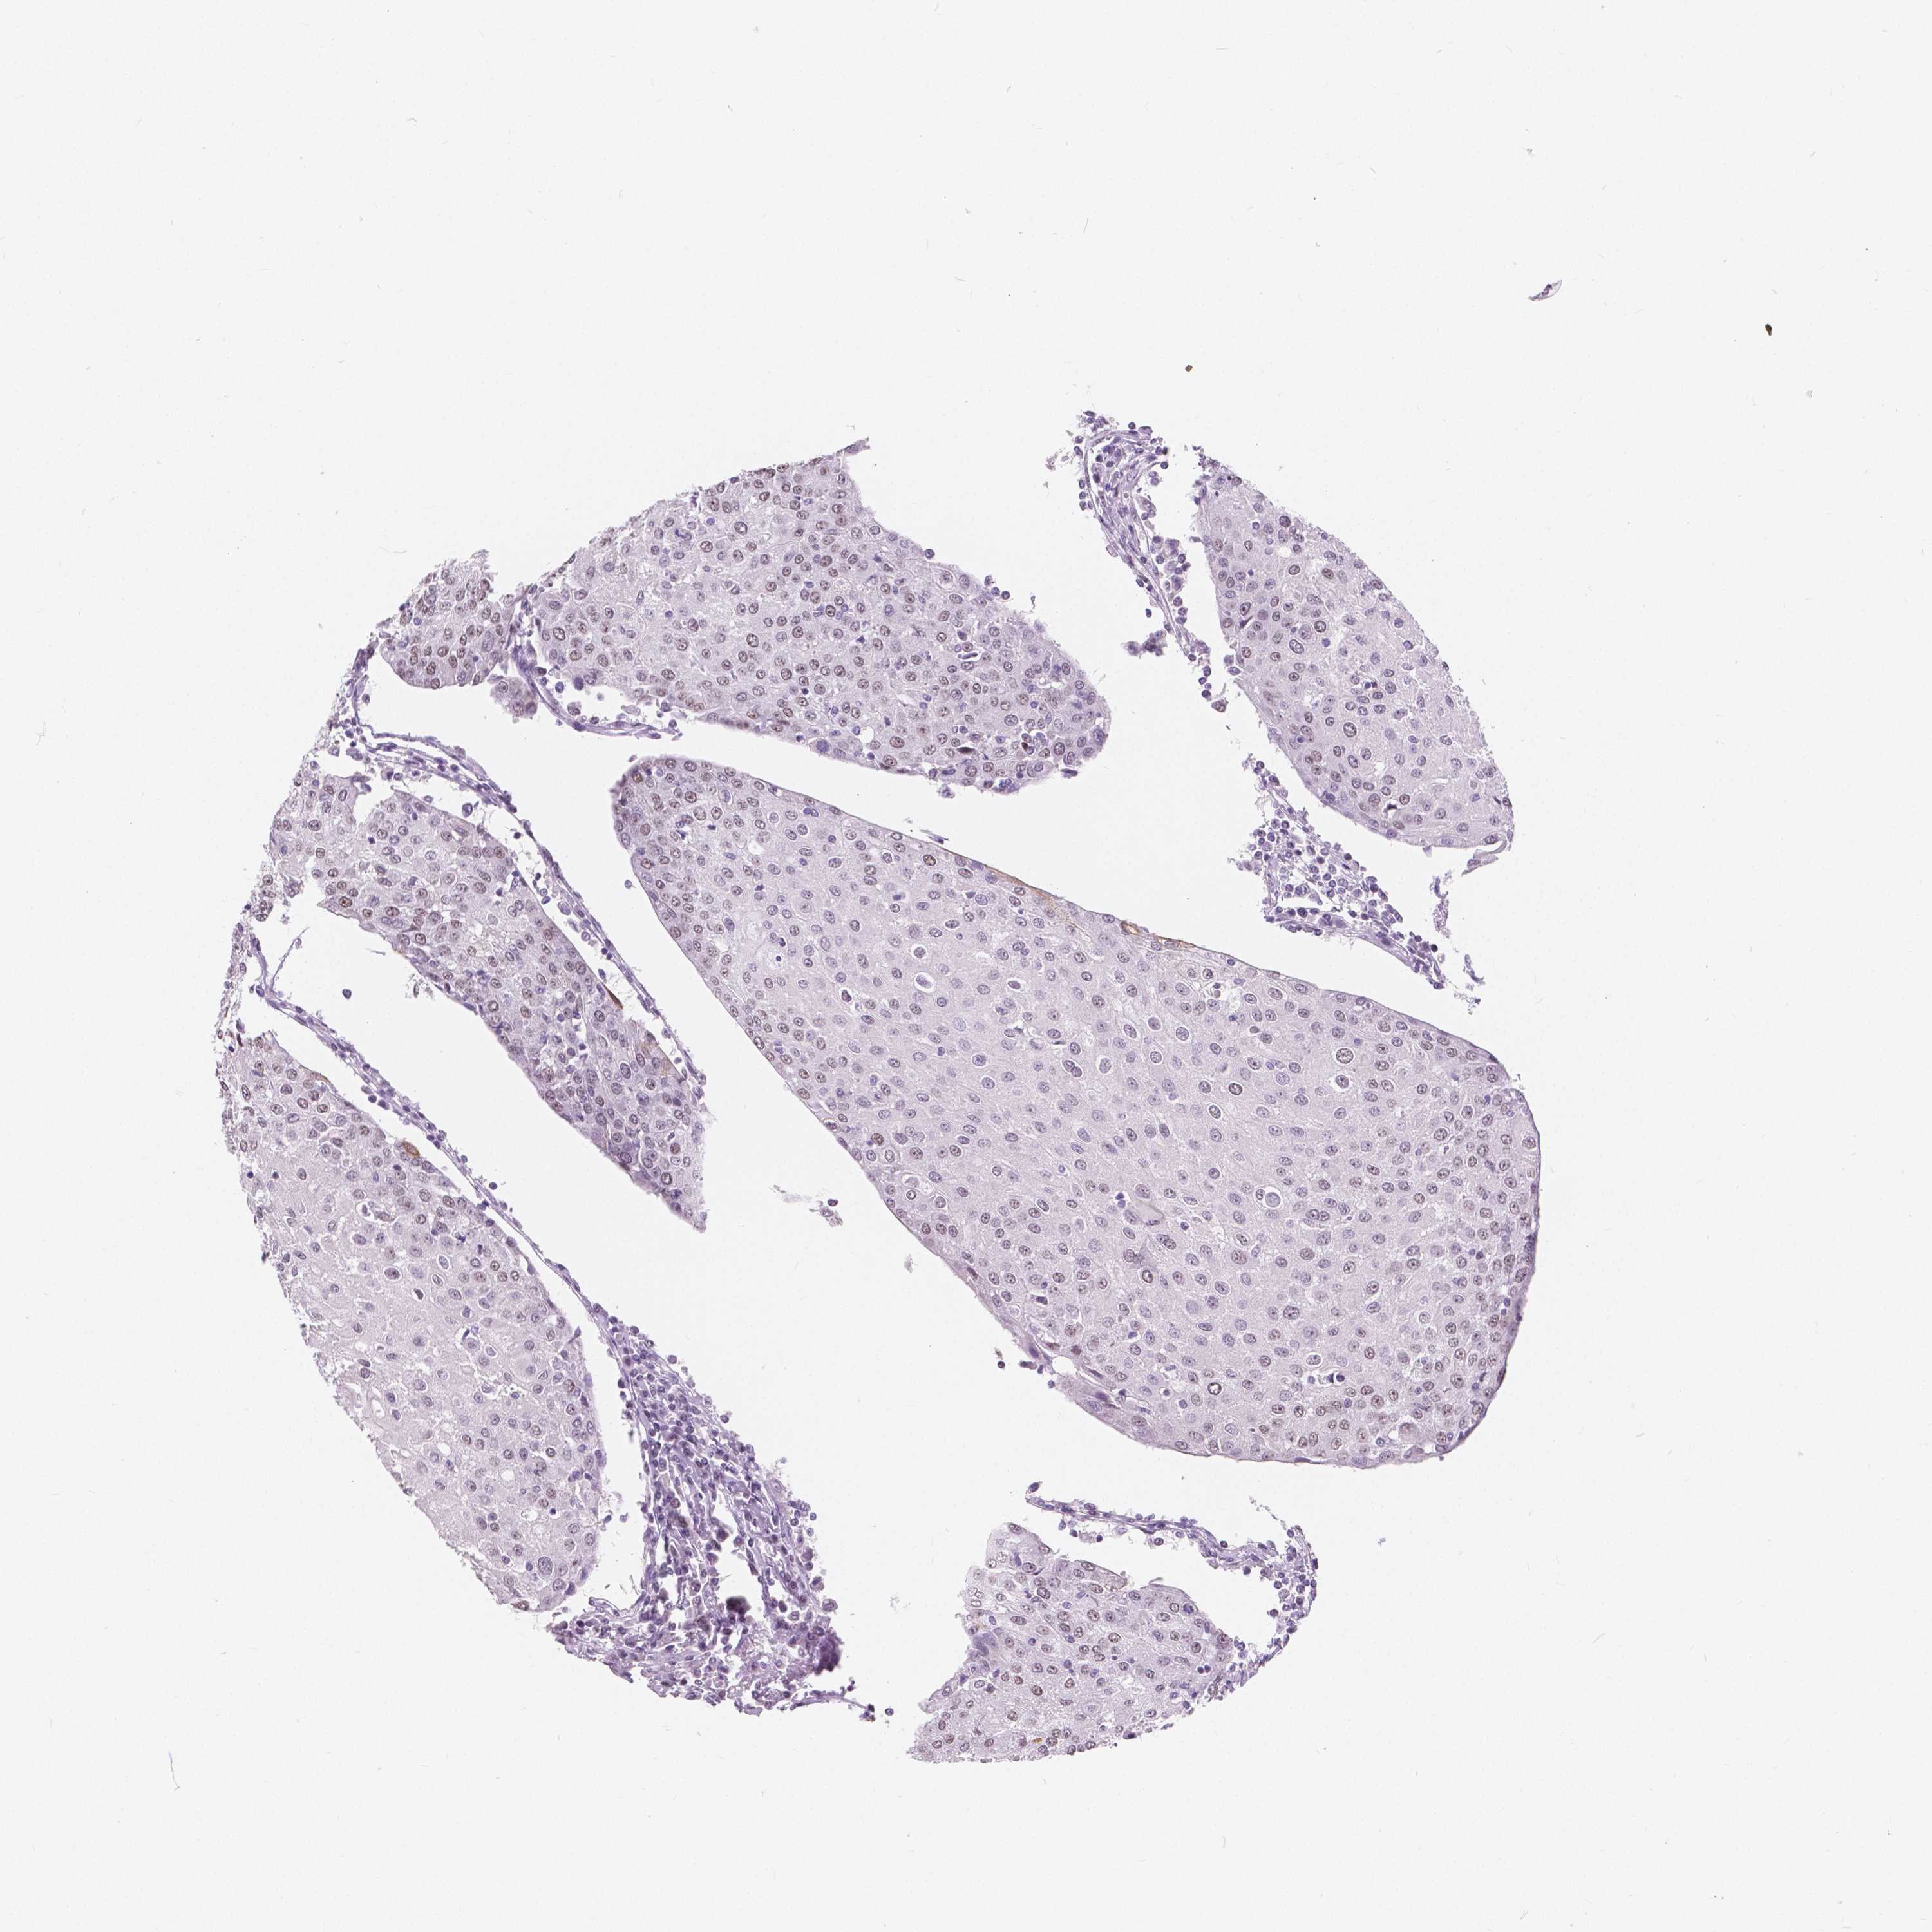

UROTHELIAL CANCER - Protein expressioni

A mouse-over function shows sample information and annotation data. Click on an image to view it in a full screen mode. Samples can be filtered based on level of antibody staining by selecting one or several of the following categories: high, medium, low and not detected. The assay and annotation is described here.

Note that samples used for immunohistochemistry by the Human Protein Atlas do not correspond to samples in the TCGA dataset.

Antibody stainingi

Antibody staining in the annotated cell types in the current human tissue is reported as not detected, low, medium, or high, based on conventional immunohistochemistry profiling in selected tissues. This score is based on the combination of the staining intensity and fraction of stained cells.

Each image is clickable and will lead to virtual microscopy that enables deeper exploration of all samples and also displays staining intensity scores, fraction scores and subcellular localization as well as patient and tissue information for each sample.

Antibody HPA037366

Antibody HPA050388

Antibody CAB032654

Urothelial carcinoma, High grade

Urothelial carcinoma, NOS

Urothelial carcinoma, Low grade